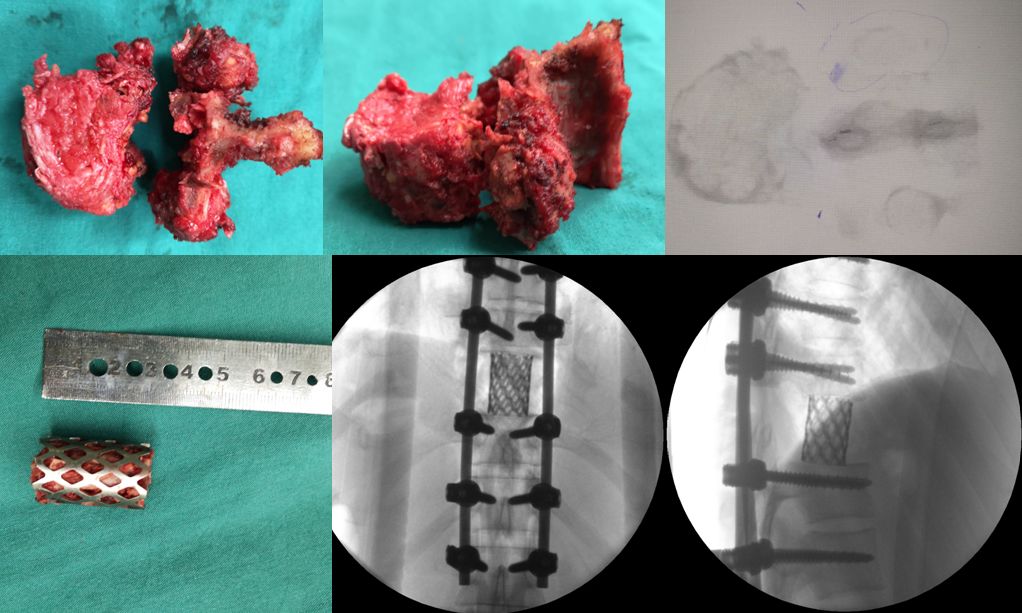

由于肿瘤周围紧挨着神经、脊髓和血管,手术既要保持肿瘤组织的完整切除,又不能牺牲重要结构,因此每一步都需要小心翼翼,张顺聪教授和丁金勇教授紧密合作,不敢有一丝懈怠,将肿瘤椎体一点一点的分离而不损伤周边正常组织。手术整整进行了9小时10分钟,在张顺聪教授和丁金勇教授专业细致的操作下,患者最终有惊无险的完成整个手术,肿瘤椎体被完美的切除,术后疗效满意。

脊柱肿瘤被完美切除,内植物位置满意